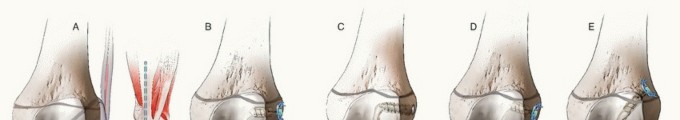

FIG 3 • Algorithm for management of complete ACL injuries in skeletally immature patients.

The approach to ACL reconstruction in the skeletally immature patient should be based on physiologic age and growth remaining. Knee size can also be considered in the feasibility of various techniques (

FIG 3

).

A variety of reconstructive techniques have been used, including physeal-sparing, partial transphyseal, and transphyseal methods using various grafts.

A variety of other physeal-sparing or physeal-respecting hybrid reconstructions have been described and may be used in cases where patients are in between the previously noted categories (

FIG 4

*). One common reconstruction technique is the epiphyseal femoral tunnel combined with the transphyseal tibial tunnel to avoid creating such an oblique femoral tunnel in a younger adolescent with significant growth remaining.

FIG 4 • Examples of repairs in male patients aged 6 to 14 years old. A. Skeletal age 6: combined intra-articular and extra-articular with iliotibial band. B. Skeletal age 8: modified Anderson. C. Skeletal age 10: all-epiphyseal.

*

D. Skeletal age 12: hybrid. E. Skeletal age 14: transphyseal.